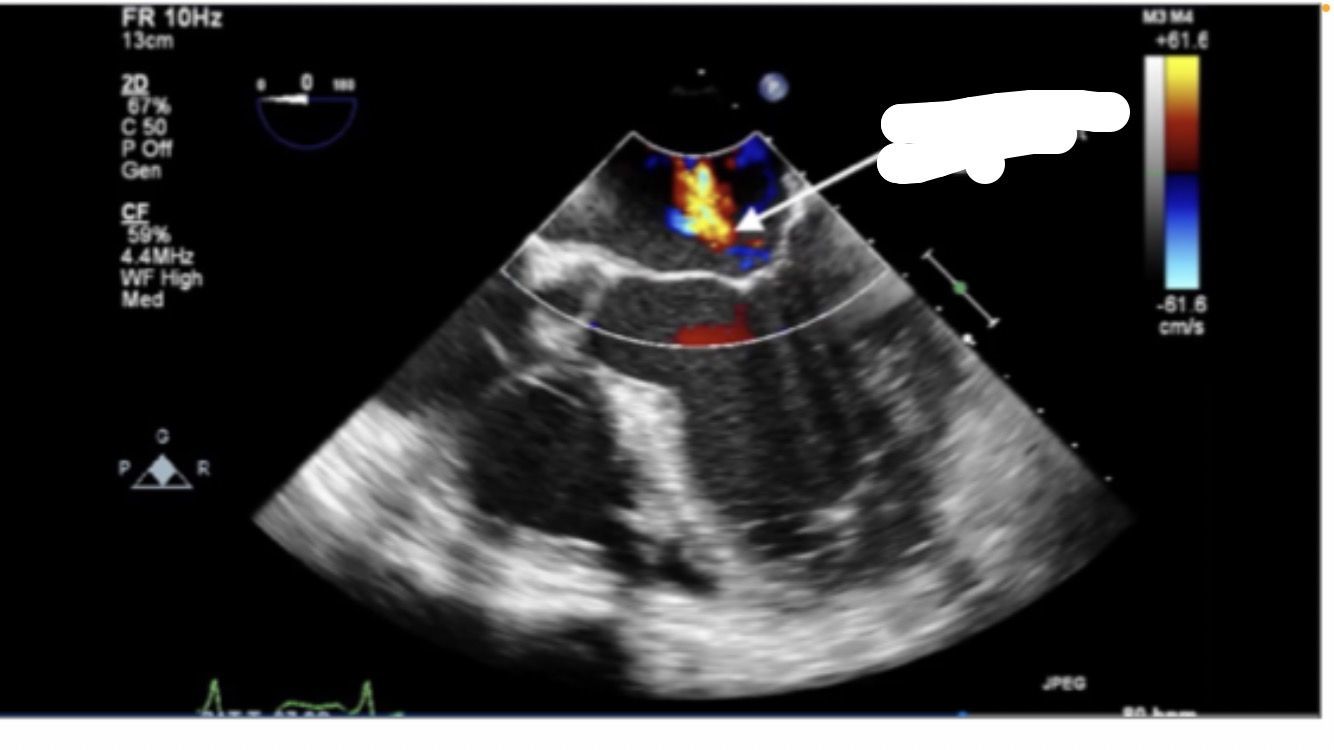

Mid-esophageal Long Axis view. LAX